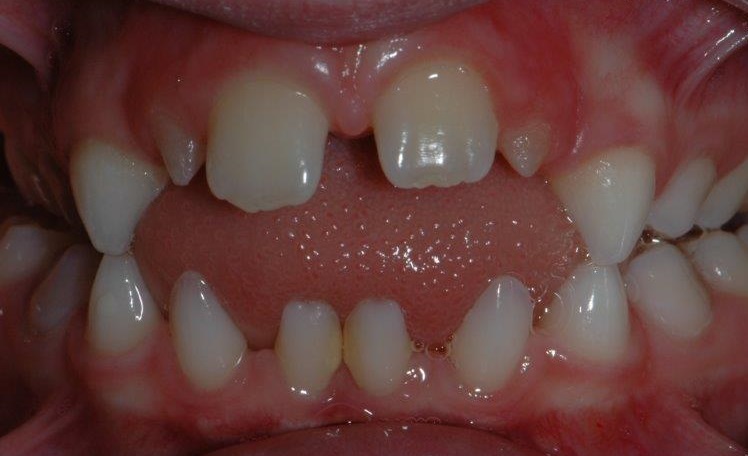

Photographie intrabuccale